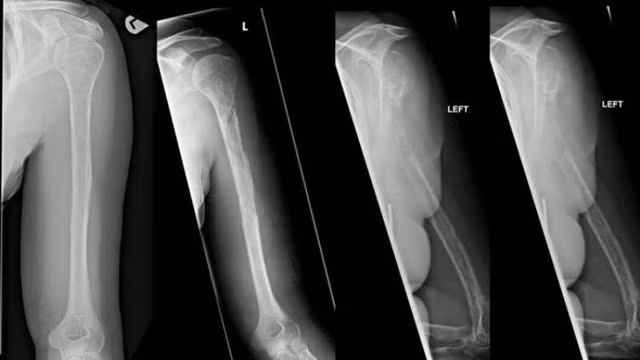

Vì tình trạng này rất hiếm nên cũng rất khó chẩn đoán. Trong trường hợp của người phụ nữ ở Edinburgh, ban đầu cô đến bác sĩ để phàn nàn về cơn đau bất thường ở vai trái. Chụp X quang cho thấy có tổn thương trên xương của cô. Điều này khiến các bác sĩ tin rằng bệnh nhân bị ung thư nhưng kết quả sinh thiết lại chứng minh phán đoán này là không chính xác.

Sau 18 tháng ròng, cuối cùng các nhân viên y tế cũng đưa ra câu trả lời. Bằng cách quan sát các ảnh chụp X quang, bác sĩ nhận thấy xương trong cơ thể người phụ nữ mờ dần sau mỗi lần quét. Nhiều thử nghiệm được tiến hành cũng đã xác nhận rằng xương của bệnh nhân biến mất theo nghĩa đen. Kỳ lạ thay, các mạch máu lại tăng trưởng thay thế cho mô xương của cô.